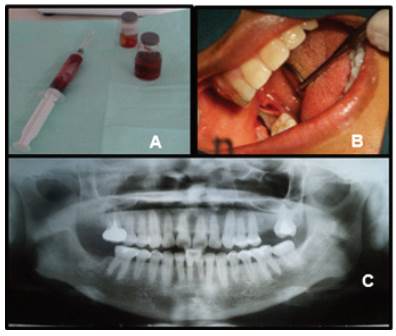

Antes de realizar la biopsia excisional, se planificó la aspiración, obteniéndose abundante líquido sanguinolento y restos de gránulos minúsculos de aparente tejido necrótico (Figura 3A), procediéndose con la enucleación total. Bajo anestesia local troncular inferior, se realizó una única incisión retromolar, para abrir colgajos vestibular y lingual, donde se aisló la lesión por completo para ser enucleada posteriormente (Figura 3B), seguido de minucioso curetaje y lavado de la cavidad ósea con abundante solución salina estéril. Para evitar recidivas se realizó exodoncia de la pieza 4.7, enseguida se suturó con polipropileno y se indicó tratamiento con analgésico, antiinflamatorio y antibióticos por vía intramuscular y enjuagatorio bucal sin alcohol.

La muestra obtenida fue colocada en solución de formol al 10% para ser enviada a estudio histopatológico (fig. 3.A). Las secciones estudiadas mostraron epitelio plano estratificado con estroma inflamado y superficie paraqueratinizada corrugada, con células basales de núcleos hipercromáticos. En algunas áreas el epitelio se separaba de la cápsula quística, confirmando así el diagnóstico definitivo de Queratoquiste Odontogénico de tipo paraqueratinizado.

El retiro de sutura y primer control posoperatorio fue realizado diez días después a la cirugía. Tres meses después se citó a la paciente para control clínico y evaluación con radiografía panorámica, mostrando excelente cicatrización y ausencia de recidiva, mostrando neoformación ósea en región de la lesión (Figura 3C). Se realizó pruebas de vitalidad pulpar en la pieza 4.6, siendo la misma positiva.